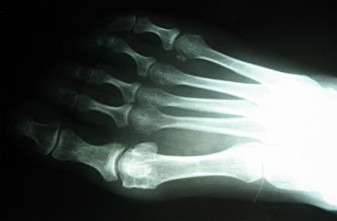

A 55-year-old diabetic patient presents with a swollen, erythematous, and warm foot. Assuming radiographs initially revealed midfoot fragmentation and subluxation, and follow-up radiographs 4 months later demonstrate absorption of fine bone debris and early fusion of large fragments. According to the Eichenholtz classification of Charcot arthropathy, which stage does this represent?

Options:

Correct Answer: Stage II (Coalescence)

Explanation:

The Eichenholtz classification describes the natural history of Charcot neuroarthropathy. Stage 0 is the inflammatory phase (erythema, edema, warmth, normal radiographs or mild osteopenia). Stage I (Fragmentation) is characterized by joint subluxation, debris formation, and fragmentation. Stage II (Coalescence) is marked by the absorption of fine debris, early sclerosis, and fusion of larger fragments as the acute inflammation subsides. Stage III (Consolidation/Remodeling) shows remodeling of the bone ends, decreased sclerosis, and a stable (though often deformed) joint.